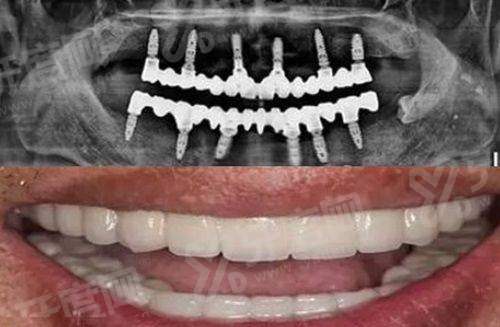

1、数字化种植技术:引进3D导板精细种植系统,术前通过CBCT扫描构建口腔三维模型,种植体植入误差可控制在0.5mm内,缩短手术时间,减少创伤。

1、张XX:主事医师,从事口腔临床工作15年,擅长复杂种植牙、牙槽骨缺损修复,曾完成半口All-on-4种植实例300+。

青岛中诺口腔医院半口种植牙价格:2万元起

青岛中诺口腔医院全口种植牙价格:3.5万元起